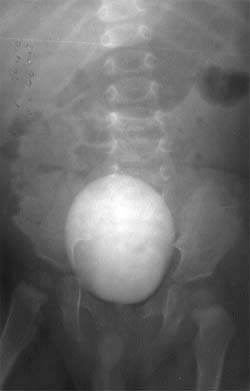

Понимание операции мочеточникового рефлюкса: всё, что нужно знать